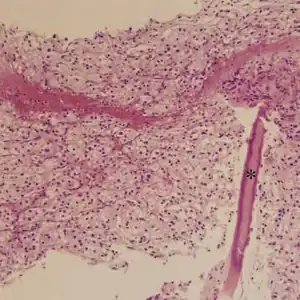

Metastatic alveolar soft part sarcoma of lumbar vertebrae

High-magnification micrograph showing the characteristic large cells with abundant eosinophilic, i.e. pink, cytoplasm and an eccentrically placed nucleus